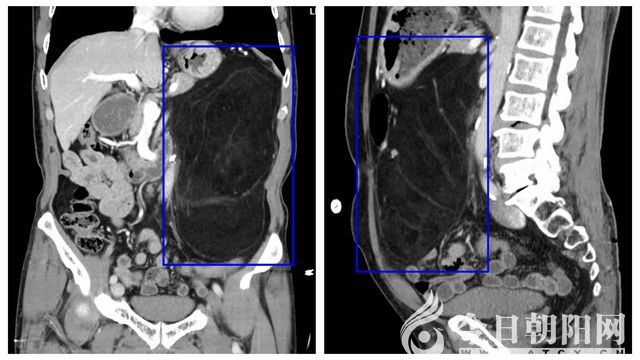

9月17日上午,市二院消化內(nèi)科門診接待了一位特殊的老先生。老先生在體檢行肝膽胰脾彩超檢査后,被告知胰腺區(qū)域大范圍顯示不清、回聲信號(hào)異常,建議進(jìn)一步就診。待行全腹CT檢查后提示:左腎外后方見條形高密度灶,腎周圍血腫或腎包膜下血腫,左側(cè)腹系膜區(qū)見巨大脂肪結(jié)構(gòu)堆積灶,腫瘤將左腎及腹膜后大血管包繞填壓,考慮巨大脂肪瘤。在沒有任何征兆的情況下,平白無故長了一個(gè)腫瘤,身體還未受任何影響,這下可急壞了老先生及家屬。在向熟人打聽及上網(wǎng)查詢后,了解到市二院陳亞光主任醫(yī)師領(lǐng)導(dǎo)的胃腸外科團(tuán)隊(duì)在這方面有著豐富的診療經(jīng)驗(yàn),便慕名來到該科室。陳亞光主任考慮老先生的疾病為“腹膜后巨大腫物”,需住院手術(shù)切除方可達(dá)到最佳的治療效果。就這樣,71歲高齡的老先生在家人的陪伴下,住進(jìn)了胃腸外科,打響了自己與疾病斗爭(zhēng)的第一槍。

隨著老先生住院后,第一個(gè)問題便來到了胃腸外科醫(yī)生面前,CT提示腎周圍血腫或腎包膜下血腫,究竟是怎樣形成的?如果腎周血腫進(jìn)一步增加,患者可能存在腎出血、腎破裂的可能,隨之而來的就是失血性休克,嚴(yán)重危及患者生命安全,手術(shù)中是否能保留患者左側(cè)腎臟等一系列問題擺在了醫(yī)生面前。科室討論后,立即給予患者完善術(shù)前相關(guān)檢查并組織全院相關(guān)科室會(huì)診。檢查及會(huì)診后結(jié)果未見血腫進(jìn)一步增加,血紅蛋自及紅細(xì)胞穩(wěn)定,術(shù)中保留左側(cè)腎臟的幾率較高,這樣大家才松了一口氣。待患者完善腹部增強(qiáng)CT后,第二個(gè)問題接踵而來,巨大的腫物幾乎占據(jù)了大部分腹腔,大面積小腸腸管受壓,同時(shí)腫瘤與周圍組織及周邊大血管關(guān)系密切,手術(shù)切除難度極高。對(duì)于此類情況,常規(guī)手術(shù)是要在腹部開一個(gè)長約25cm的大切口,將腫瘤切除取出,但是考慮到患者的年齡和特殊血型(B型Rh陰性血,俗稱熊貓血),行開腹手術(shù)創(chuàng)傷大、恢復(fù)慢,因此,采用腹腔鏡微創(chuàng)手術(shù)切除更為合適,用最小的創(chuàng)傷,獲得最快最佳的治療效果。